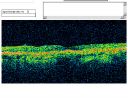

OCT SCAN: The OCT scan shows retinal atrophy in both eyes. The average central foveal thickness in the right eye is 170 microns with a volume of 4.85 mm3. The left eye has 161 microns with a volume of 5.18 mm3. The line scans show loss of the photoreceptor integrity around the macula in both eyes. Photos confirm clinical findings.